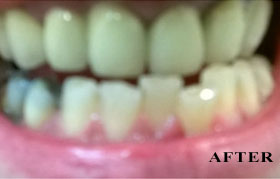

PHOTO GALLERY

Cosmetic, Reconstructive & Athletic Dental Surgeon - Smile Design / Implants